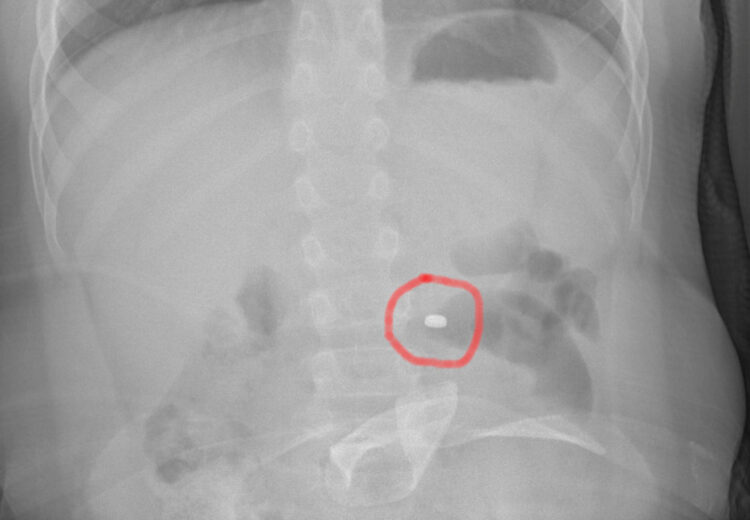

La famiglia, naturalmente spaventata, dopo una prima valutazione al PS della propria città, è stata indirizzata all’Ospedale Cannizzaro di Catania. Qui i medici hanno compreso il pericolo e applicato le linee guida riferite precisamente all’ingestione di una pila a bottone. Eseguita la radiografia dell’addome che ha messo in evidenza la presenza e la localizzazione del corpo estraneo, il bambino è stato condotto in sala operatoria dove gli endoscopisti, con l’assistenza degli anestesisti, hanno potuto estrarre in sicurezza il piccolo oggetto, prima che esso potesse causare conseguenze più importanti. Dopo una notte in osservazione, tornato in piena salute, il bimbo ha fatto rientro a casa con i genitori.